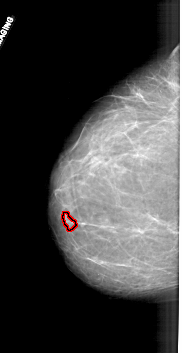

A_1711_1.RIGHT_CC

LEFT_CC LINES 6001 PIXELS_PER_LINE 3091 BITS_PER_PIXEL 12 RESOLUTION 43.5 OVERLAY

FILE: A_1711_1.LEFT_CC.OVERLAY

TOTAL_ABNORMALITIES 1

ABNORMALITY 1

LESION_TYPE MASS SHAPE LOBULATED MARGINS CIRCUMSCRIBED

ASSESSMENT 4

SUBTLETY 3

PATHOLOGY BENIGN

TOTAL_OUTLINES 1

BOUNDARY